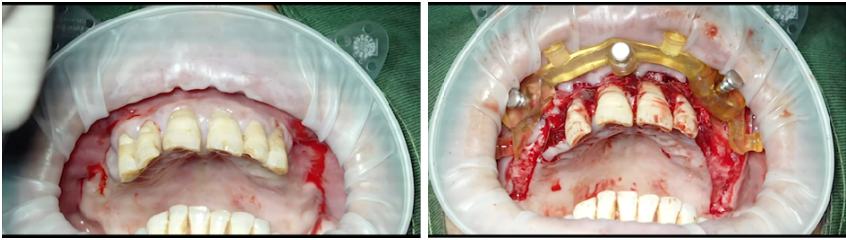

即刻修复3个月后:

上颌边缘骨稳定,行下颌后牙区种植,下颌植入4颗中科安齿种植体

即刻修复5个月后:

边缘骨稳定,上下颌同期行永久修复

永久修复3年随访:

上下颌边缘骨稳定,零骨吸收

病例总结

通过修复后口内照观察到,美学效果良好,无基台种植体配合性能相关的周围炎。通过医学影像观察到,修复三年后种植体周围无骨吸收,患者非常满意。